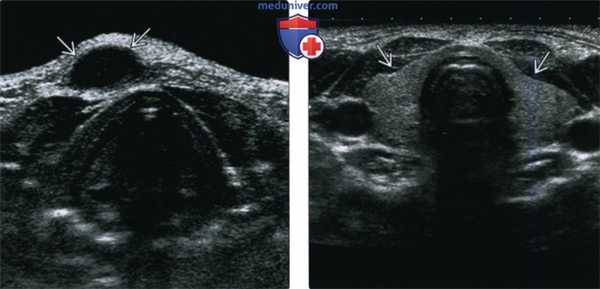

(Слева) На поперечной сонограмме в подкожных тканях визуализируется гипоэхогенное объемное образование с ровными краями, расположенное парамедианно справа, спереди от подподъязычных мышц. Образование было оперативно удалено, подтвердилась КЩЯП.

(Справа) На поперечной сонограмме у ребенка с подозрением на кисту щитоязычного протока в области предполагаемой локализации в нижних отделах шеи визуализируется щитовидная железа, имеющая нормальный вид (состоящая из двух долей). У всех пациентов, обследуемых на предмет КЩЯП, важно документально отразить наличие щитовидной железы в ожидаемом месте и отсутствие патологических изменений с ее стороны.

(Слева) УЗИ в поперечной плоскости у ребенка с вновь появившимся объемным образованием передних отделов шеи слева: визуализируется патологический гетерогенный очаг без признаков кровотока при цветовой допплерографии, но с выраженными эхогенными включениями, наличие которых позволяет заподозрить дермоид или рак в КЩЯП. При патоморфологическом исследовании подтвердилась киста, не осложненная кровоизлиянием, инфекцией, без признаков наличия злокачественной опухоли.

(Справа) УЗИ в поперечной плоскости у восьмилетнего ребенка: визуализируется типичная подподъязычная КЩЯП в виде анэхогенного объемного образования, расположенного парамедианно и обусловливающего легкое сдавливание левой доли щитовидной железы, в остальном выглядящей нормальной.